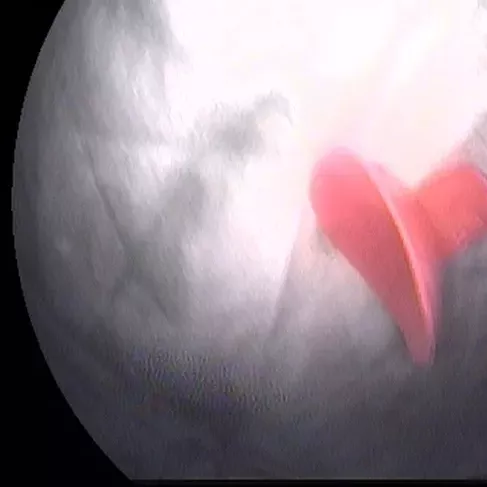

小编再带您看看这些年我院胃肠镜室从孩子身体里取出过的异物,对照一下,您家孩子接触过几样?

玩具枪子弹